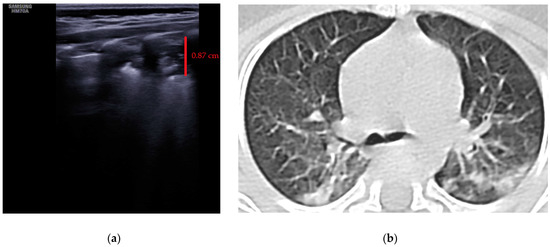

The LUS score (LUSS) varied between 4 and 18 points from a maximum of 36 points. The mean was 12.21 ± 3.56 (S.D), while the 95% CI for the arithmetic mean was 10.49–13.93. The changes described at lung ultrasound that appeared in a minimum of one area/neonate were:

- Erasing of A-lines—with a prevalence of 100%;

- Sparse B-lines (Figure 3a)—100%;

Figure 3. The lung ultrasound showed (a) sparse B-lines with small zones of pleural irregularities corresponding to a LUSS = 1; (b) confluent B-lines with aspect of ‘white-lung ‘corresponding to LUSS = 2. - Confluent or coalescent B-lines (Figure 3b)—57.89%;

- ‘White-lung’ (Figure 3b)—36.84%;

- Pleural abnormalities (irregularities, thickening, fragmented)—68.42%;

- Subpleural consolidation <1 cm (Figure 4a,b)—31.57%;

Figure 4. (a) The lung ultrasound showed a small consolidation area with the length <1 cm corresponding to a LUSS = 2; (b) The CT exam revealed bilateral consolidations in the posterior segments. - Pleural effusion—5.26%.

- No large consolidation in the subjects included was reported.